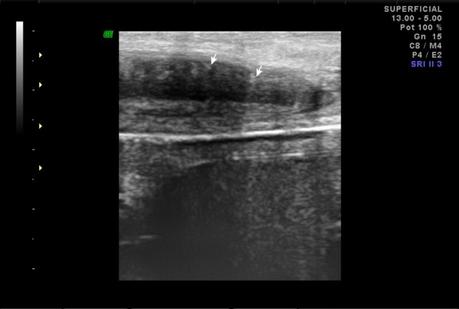

A nivel de base del pené, entre los cuerpos cavernoso y esponjoso en su porción central se observa la presencia de calcificación, que mide 2.2 mm. En tercio distal del pené, a nivel de cuerpos cavernosos con presencia de calcificación que mide 1.8 mm.

A NIVEL DE BASE Y TERCIO DISTAL DEL PENÉ, EN CUERPOS CAVERNOSOS CON PLACAS A RELACIÓN A ENFERMEDAD PEYRONIE.